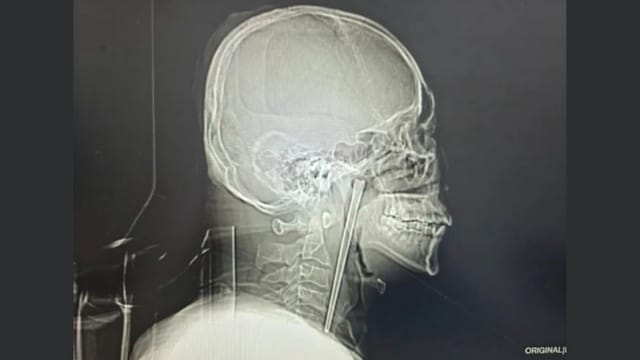

怕开刀拖延治疗 中国男子误吞金属筷子八年终取出